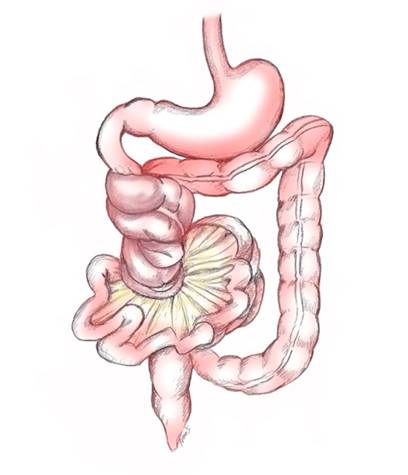

Midgut volvulus is a complication of malrotation in which clockwise twisting of the bowel around the superior mesenteric artery (SMA) axis occurs because of the narrowed mesenteric attachment. Volvulus can result in bowel obstruction, ischemia, or infarction but is not defined by the presence of or absence of obstruction or ischemia.

In the neonatal period the normal mesentery has a broad base, which extends from the left upper quadrant at the duodenojejunal junction (ligament of Treitz) to the cecum in the right lower quadrant. Midgut malrotation refers to a spectrum of congenital intestinal anomalies of position resulting from a non-rotation or an incomplete counterclockwise rotation of the primitive intestinal loop around the axis of the SMA during fetal development. The failure to complete rotation results in a narrow base of the mesentery, which can predispose the neonate to Volvulus of the midgut (the subsequent twisting of the bowel around the SMA)

Surgical (Ladd procedure) - The volvulus has to be reduced, and the nonviable bowel to be resected. Transection of Ladd bands is done and the base of the mesentery is surgically broadened.